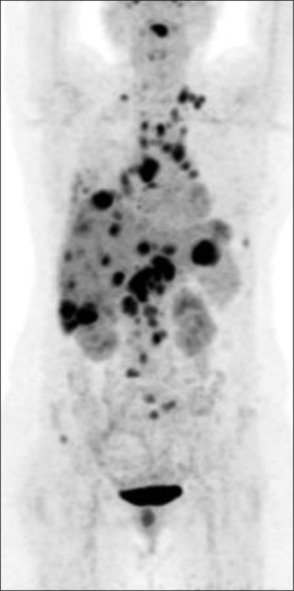

Lung cancer is the leading cause of cancer and cancer-related deaths, and India ranks the fourth highest country. Lung cancer is a highly aggressive malignancy with a tendency for rapid progression, making early detection and prompt treatment essential for improving patient outcomes. Lung cancer can spread locally into surrounding tissue as well as travel through lymphatics to other parts of the body, most often to bone, brain, liver, and adrenal glands. Metastasis to pituitary and pineal glands is extremely rare. The differential diagnosis for pituitary metastasis could be pituitary adenoma where lesion usually lies at the anterior aspect of pituitary fossa, whereas metastasis is seen at the posterior aspect. There is a paucity of published literature, with only a few cases reported of pituitary and pineal gland metastasis. Hence, to add to the literature, we present a case of pituitary metastasis in an older woman with lung cancer.